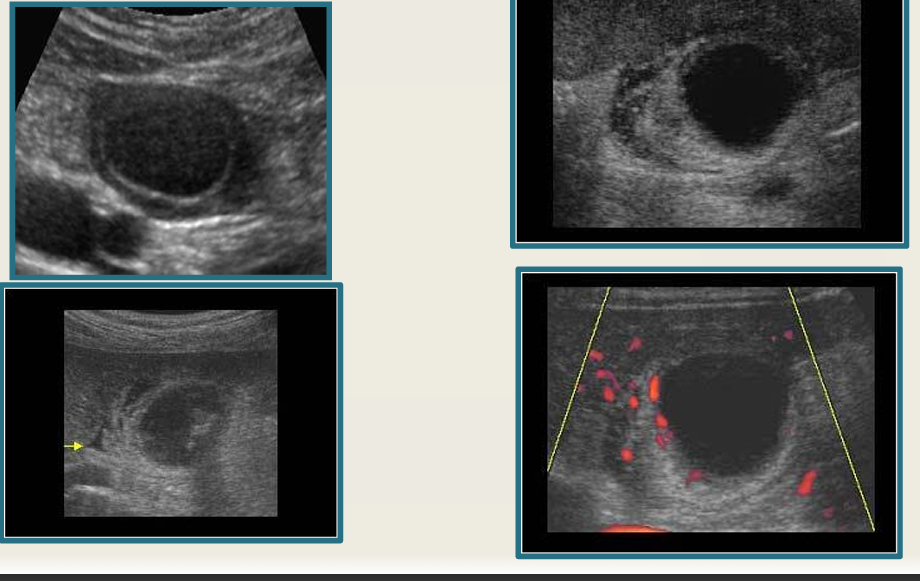

cholecystitis